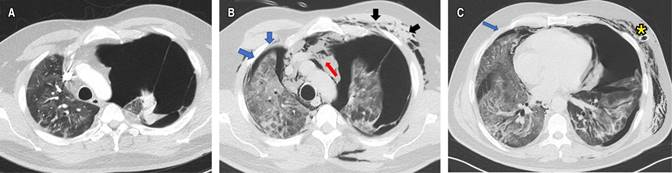

La radiografía de tórax demostró un neumotórax derecho con colapso de 50% del hemitórax ipsilateral (Figura 1A), que requirió manejo con toracostomía cerrada derecha y expansión completa pulmonar en los controles radiográficos. La angiotomografía (angio-TC) de tórax descartó tromboembolismo pulmonar (TEP) y evidenció opacidades en vidrio esmerilado (OVE) bilaterales, de distribución periférica, subpleural, con engrosamiento septal interlobulillar y enfisema subcutáneo derecho (Figuras 1B y C). Se consideró neumonía por COVID-19, y su manejo consistió en dexametasona intravenosa (IV) de acuerdo al ensayo RECOVERY,20 oxígeno (FiO2 32%) y analgesia. A las 72 horas se retiró el tubo de tórax. Los laboratorios de control mostraron disminución de los marcadores de severidad, con egreso a los siete días de estancia hospitalaria. En el seguimiento a los tres meses (Tabla 1), la puntuación de la escala de disnea modificada del Medical Research Council (mMRC) fue de cero, sin alteraciones en las pruebas de función pulmonar, con OVE residuales en la tomografía control.

Figura 1: Radiografía de tórax, proyección posteroanterior. A) Neumotórax derecho. B, C) Angio-TC de tórax, ventana para pulmón, plano axial. Se observa cámara de neumotórax (flecha negra), vidrio esmerilado de predominio en lóbulos inferiores, tubo de tórax (asterisco) y enfisema subcutáneo derecho.

La angio-TC de tórax fue negativa para TEP, con evidencia de OVE del lado derecho y neumotórax contralateral que colapsaba 90% del pulmón (Figura 2A), por lo que se realizó una toracostomía cerrada izquierda de urgencia, sin lograrse la expansión pulmonar. Al tercer día de estancia hospitalaria, presentó deterioro de la oxigenación que requirió inicio de suplencia de oxígeno por cánula de alto flujo e ingresó a la unidad de cuidados intensivos (UCI) sin requerimiento de VM. La TC de alta resolución control (Figuras 2B y C) demostró OVE, áreas de crazy paving de predomino derecho, neumotórax apical derecho pequeño (< 10%), neumomediastino y enfisema de los tejidos blandos del hemitórax izquierdo. Fue llevado a una segunda toracostomía cerrada a nivel apical izquierdo por cirugía de tórax, con persistencia del colapso pulmonar ipsilateral, por lo que se realizó decorticación y pleurectomía parietal por toracoscopia, con expansión satisfactoria. La patología reportó pleuritis crónica (Figura 3). Se indicó manejo conservador del neumotórax derecho, con expansión pulmonar en imágenes posteriores.

Figura 2: Angio-TC, ventana para pulmón, corte axial: A) Neumotórax izquierdo y opacidades en vidrio esmerilado. B, C) TC (tomografía computarizada) de tórax control, cortes axiales con neumotórax derecho (flechas azules), neumomediastino (flecha roja), persistencia del neumotórax izquierdo (flecha negra), enfisema subcutáneo y patrón de crazy paving. Se observa además tubo de tórax (asterisco).